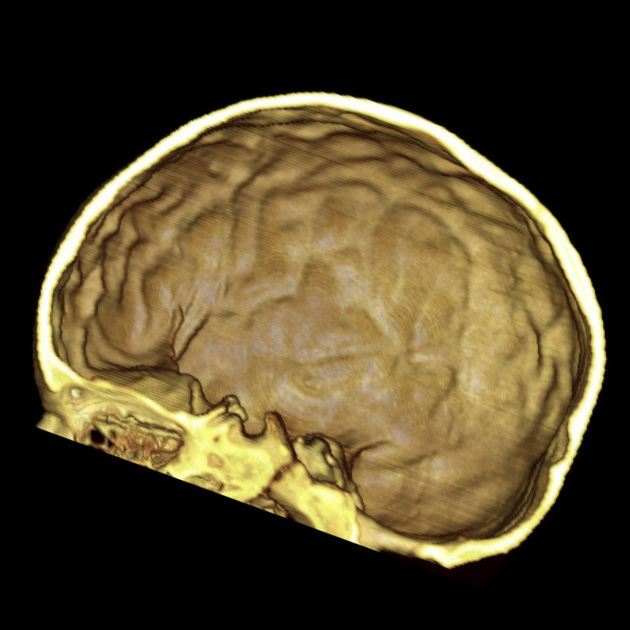

Scaphocephaly (also known as dolichocephaly) is the MOST COMMON FORM of craniosynostosis, where premature closure of the sagittal suture results in an impediment to the lateral growth of the skull while anteroposterior growth continues, producing a classic elongated, yet narrow, skull.

Marfan syndrome (both are tall and skinny)

Normal IQ. No hydrocephalus.